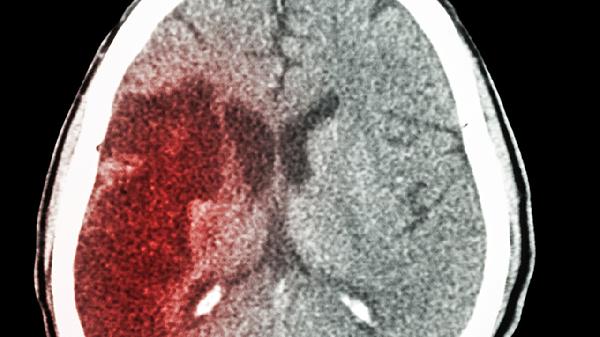

脑出血患者夏季需重点防范高温诱发血压波动,可通过调整环境温度、科学补水、适度运动、规律用药及监测体征等方式安全度夏。

脑出血患者若出现突发剧烈头痛、单侧肢体无力或言语含糊等症状,应立即平卧休息并测量血压,血压超过180/120毫米汞柱或症状持续10分钟不缓解时需紧急就医。夏季需特别注意避免从高温环境突然进入低温空调房,温差过大易导致血管痉挛。洗澡水温应接近体温,时间控制在10分钟内,淋浴后及时擦干避免受凉。对于遗留肢体功能障碍的患者,家属应协助每2小时翻身一次,保持皮肤清洁干燥,预防褥疮和肺部感染。